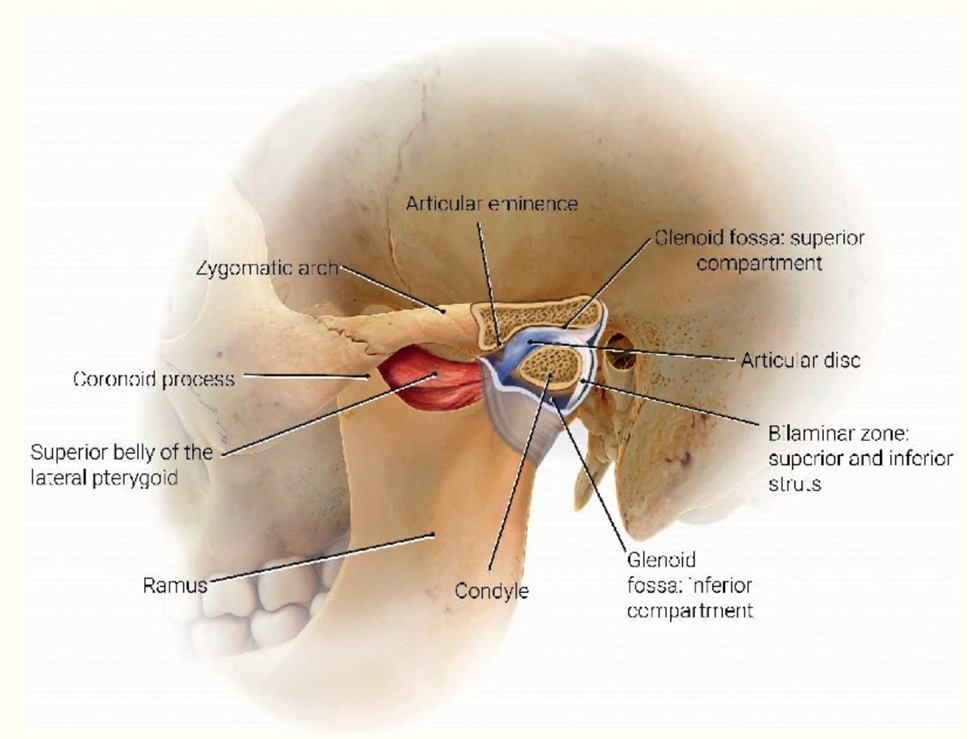

The TMJ is a bi-arthroidal hinge joint and is the articulation between the glenoid/mandibular fossa of the temporal bone and the mandibular condyle. (Figure 1).8

Figure 1. Anatomy (Artist: Judy Rubin)

From: Friedman SN, Grushka M, Beituni HK, Rehman M, Bressler HB, Friedman L. Advanced Ultrasound Screening for Temporomandibular Joint (TMJ) Internal Derangement. Radiol Res Pract. 2020:1809690. Published 2020 May 4. doi:10.1155/2020/1809690 (Used with permission)

The joint allows multiple complex jaw movements such as chewing, talking, and yawning.

The TMJ contains fibrocartilaginous surfaces and an articular disc, which divides the joint into superior and inferior articular cavities, lined by separate superior and inferior synovial membranes.

The joint is surrounded by a capsule, a fibrous membrane that surrounds the joint and attaches to the articular eminence, the articular disc, and the neck of the mandibular condyle.

The articular disc is attached to the condyle and to the collateral ligaments. The anterior disc attaches to the joint capsule and the superior head of the lateral pterygoid muscle. The posterior portion of the disc attaches to the mandibular fossa and is referred to as the retrodiscal tissue.

The retrodiscal tissue is highly innervated and is often a major contributor to pain generation in TMD.